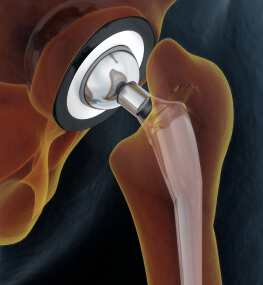

- Ендопротезування суглобів.

Заміна суглоба - операція не з простих, але сьогодні її роблять настільки часто, що для кваліфікованого лікаря в її проведенні немає нічого складного.

Ендопротезування кульшового суглоба (ціна є в прайсі) відновлює повністю функції нижніх кінцівок і дозволяє людині вільно, без дискомфорту пересуватися. Адже пошкодження тазостегнового суглоба призводить до того, що людина повністю перестає пересуватися через сильний біль.

Крім операції під назвою - ендопротезування кульшового суглоба, ціна на яку цілком доступна у нас, досить-таки часто в госпіталі проводиться і заміна колінного суглоба (ціна залежить від типу операції). Заміна суглоба в коліні - одна з найбільш затребуваних операцій.

Ендопротезування колінного суглоба в залежності від того який ступінь пошкодження тканин, може бути тотальною або частковою.

Операція по заміні суглоба є абсолютно безпечною. При цій процедурі використовується високоякісний протез, який підбирається індивідуально під кожного пацієнта.

Операція, яка позбавляє від постійного болю - заміна суглоба (ціна залежить від місця локалізації та типу операції) поверне людину до колишнього життя, адже виконується за допомогою нових технологій, що гарантують швидке одужання.